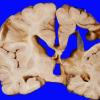

Hypoxia-Ischemia, fetal-neonatal

Porencephaly (2)